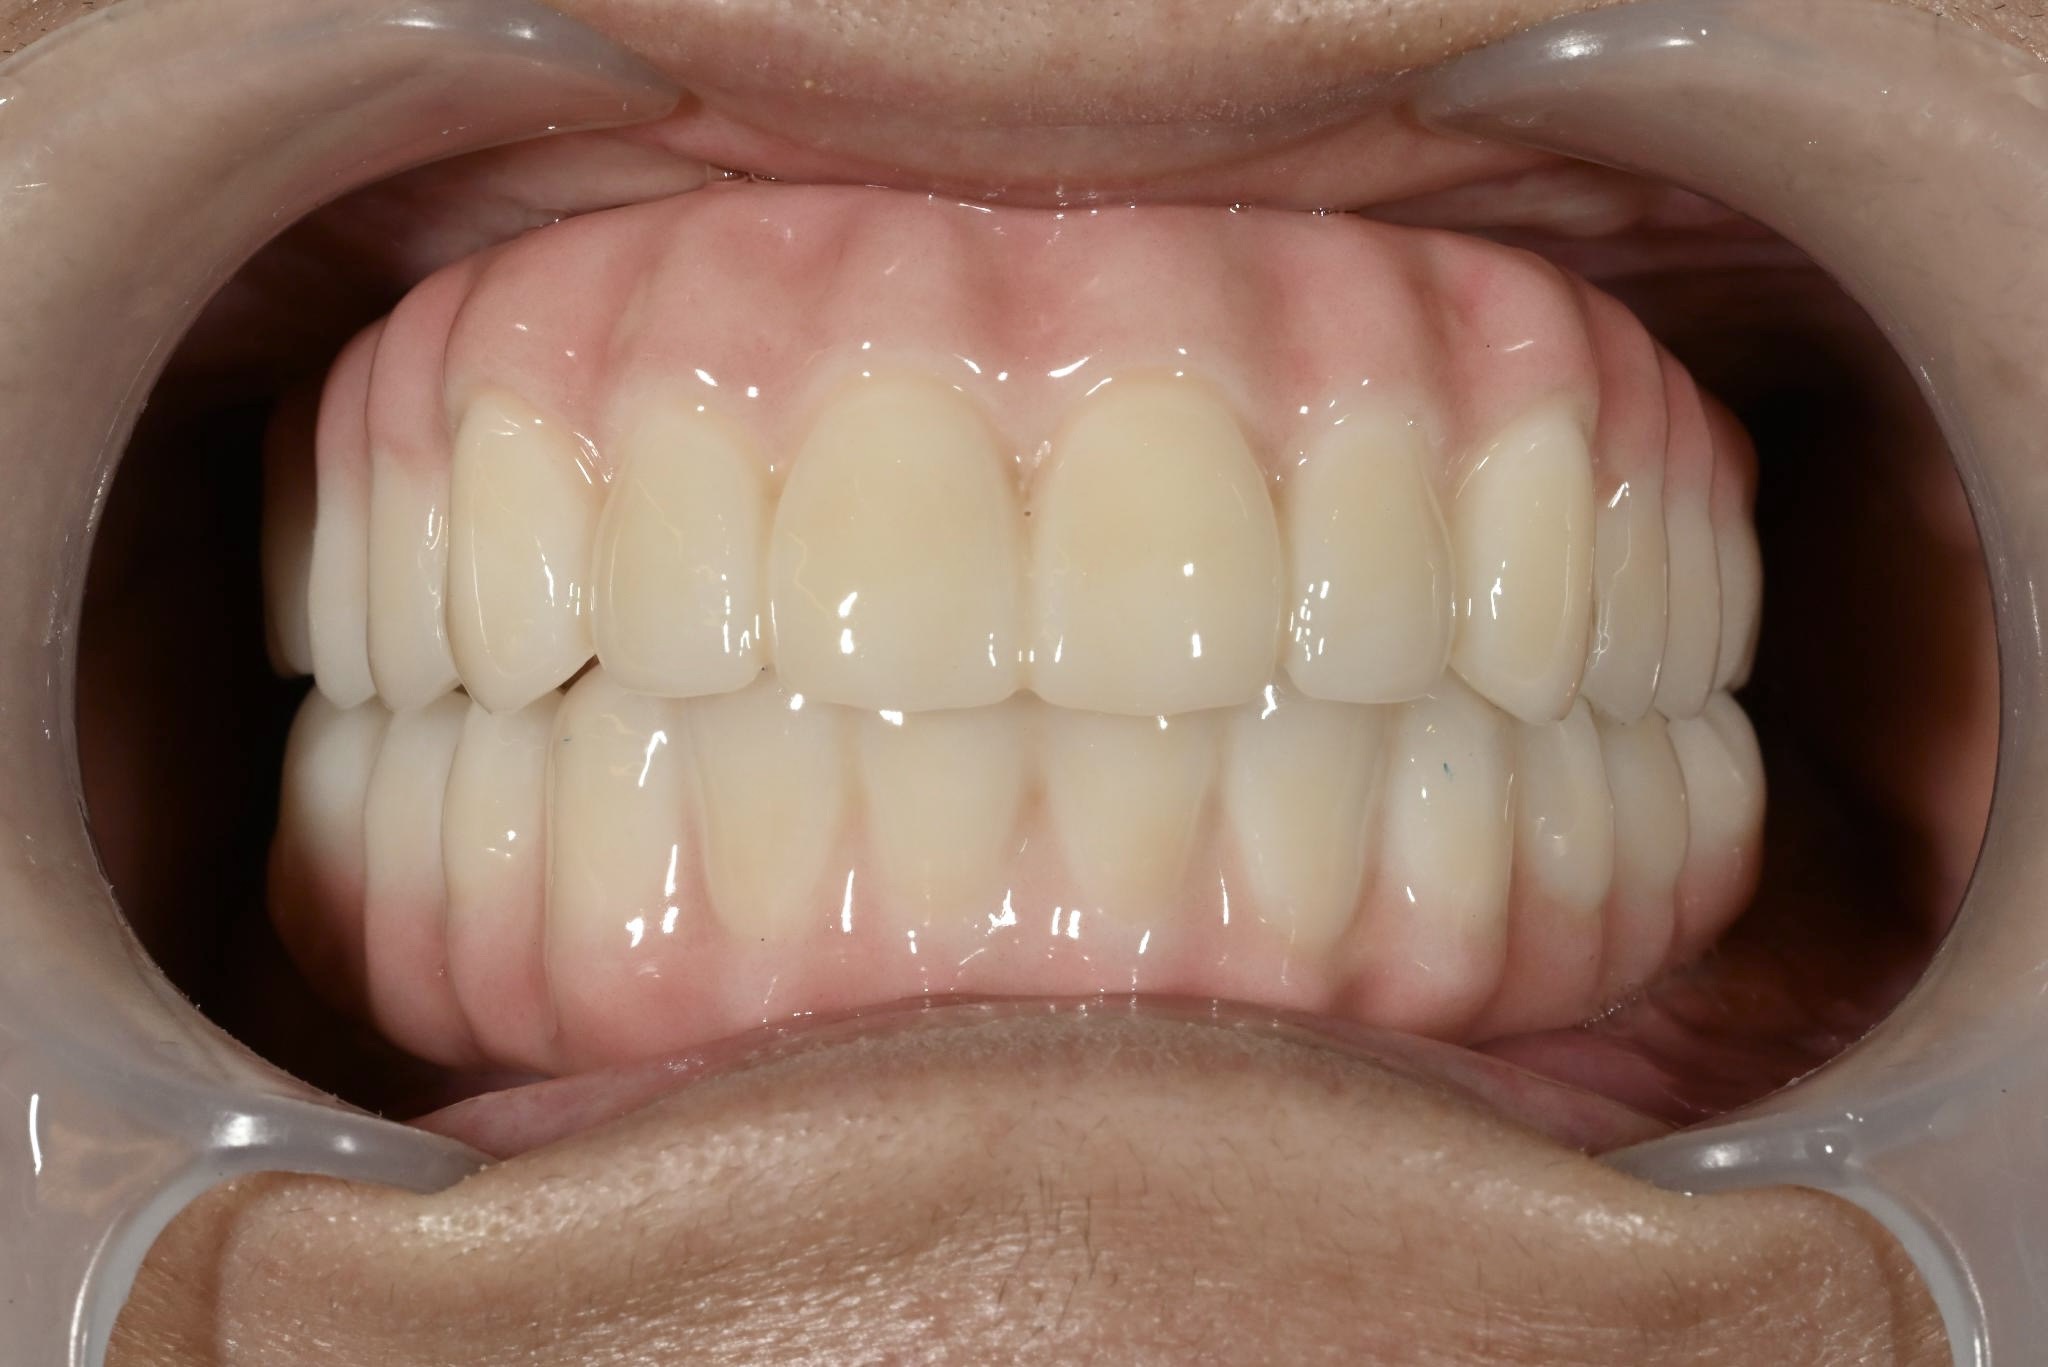

術後

内容 :上下顎オールオン4ザイゴマ2

費用 :4,963,200円

※モニター価格

期間 :半年

リスク:出血・腫れ・痺れ・痛み